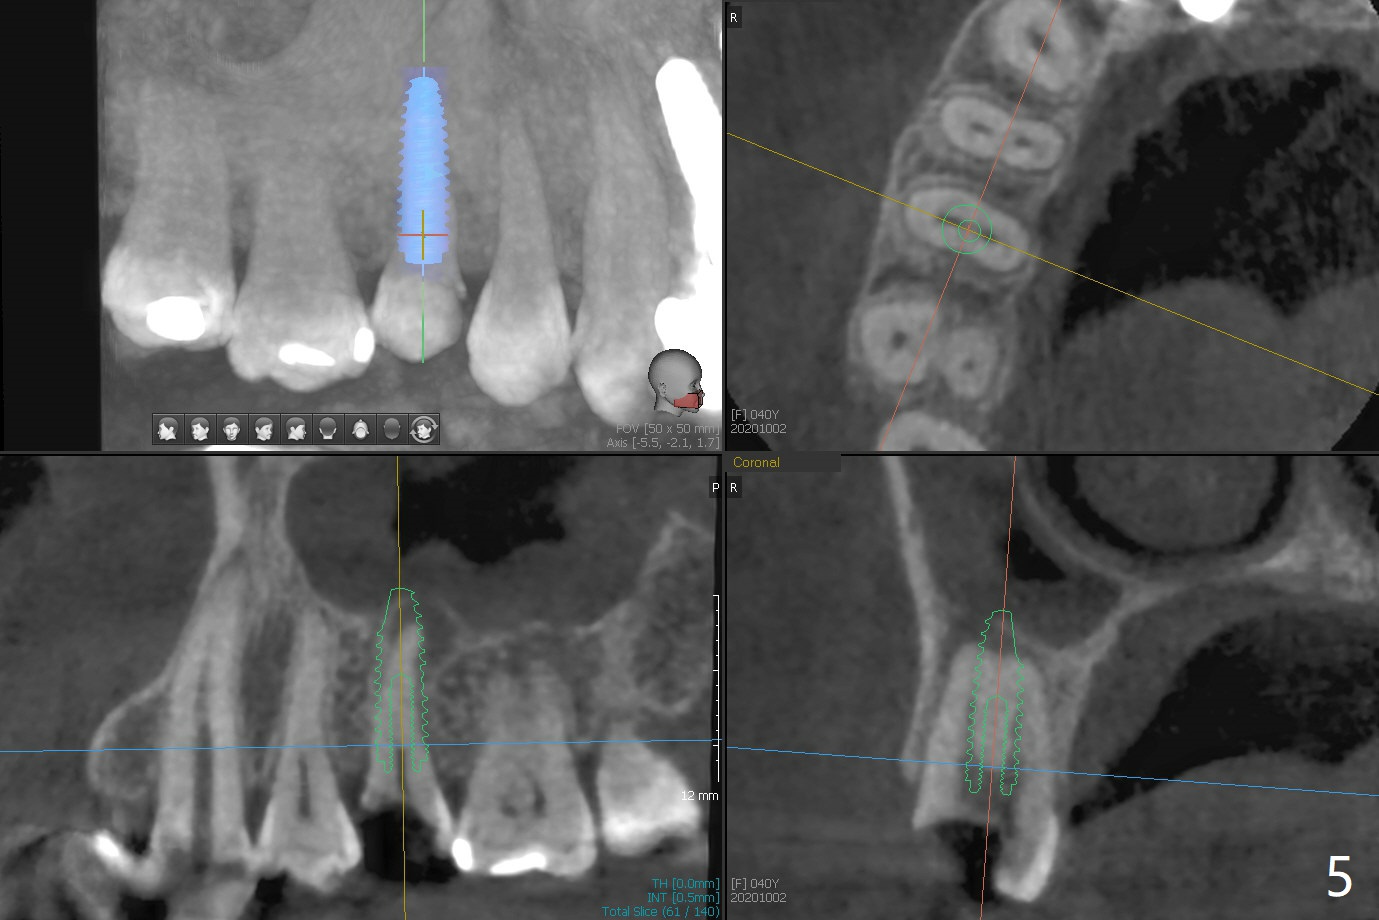

40岁女右上5树脂脱落,少许龋齿,近中边缘稍微龈下(图一:^),轻微叩痛(*)。经过商讨,她选择拔除植牙。CT检查显示上颌窦膜增厚(图二:*),为了减少术后上颌窦炎,第一,Z Pack(上呼吸道广谱抗菌素)和Medrol Dose Pack(激素)处方已开;第二,拔牙后(图三),将PRF膜推入上颌窦(图四:橘黄色),然后粘性骨块(红色圆圈);第三,植体长度刚好穿过窦底板(图五:11.5毫米)。Return to No Deviation 手术 No Neighboring Caries No Antibiotic 8, 10,30/31,19 Armaments 提升 Xin Wei, DDS, PhD, MS 1st edition 10/02/2020, last revision 03/28/2021